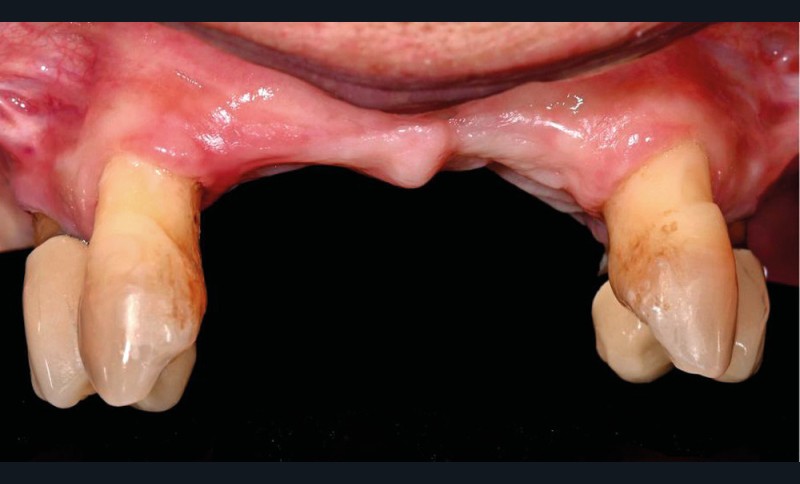

Une patiente de 62 ans, non fumeuse Asa1, porteuse d’une prothèse amovible partielle (PAP) mandibulaire et maxillaire, souhaite bénéficier d’une solution fixée. Il persiste au maxillaire 13, 23, 14 et 24, associées à une forte résorption type FP3 [1, 2] (fig. 1).